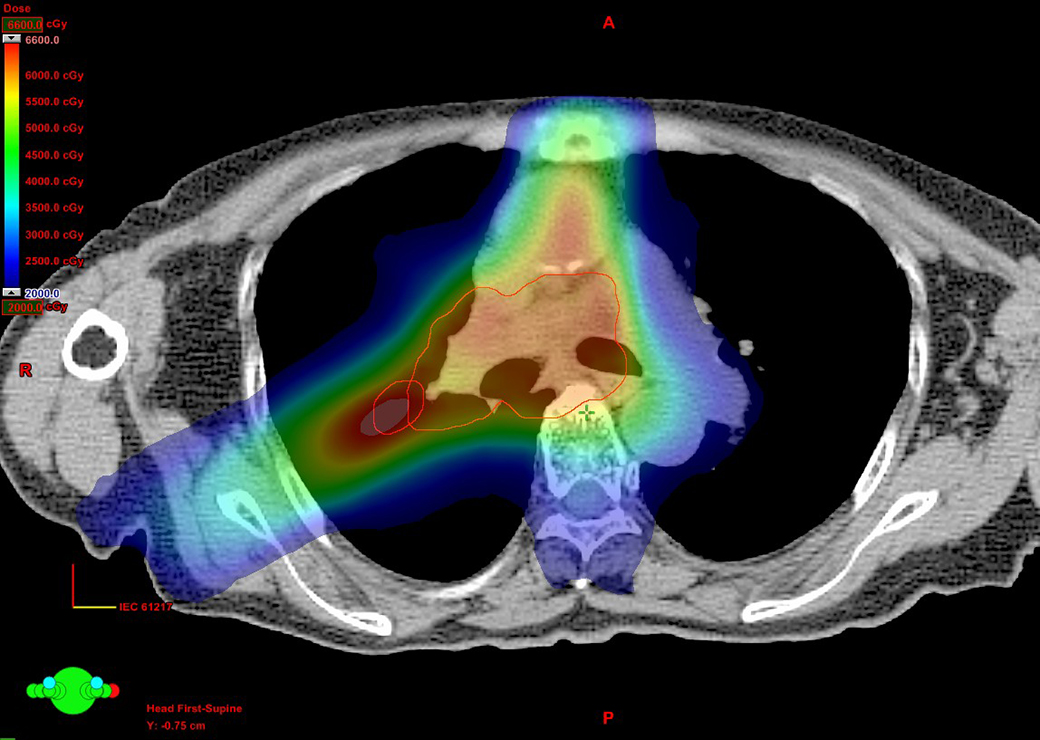

左のグラフは一般的な方法(紫色点線)と当院の方法(赤色実線)とで、がん、治療範囲、周囲の正常臓器にかかる放射線量を示しています。 一般的な方法は、がんを含めた治療範囲に均一に放射線をあてるコンセプトを採用しています。一方で、当院が考案した方法3)は、周囲の正常臓器にかかる放射線量は一般的な方法と同程度に抑えつつ、がんを中心にした治療範囲には非常に高い放射線量を照射することが可能です。

(左上)左肺に発生した肺がん、(中央上)一般的な方法, 48Gy/4回 アイソセンター処方

(右上)当院の方法, 50Gy/5回 60%辺縁処方,

図は同じ早期肺がん患者さんに対して2種類の照射技術/考え方で体幹部定位放射線治療を行った場合の体の中の放射線量の分布(20グレイ1<青>~80グレイ<赤>)をグラデーションで表しています。正常肺・がんにかかる放射線量は施設で差があることが見て取れます。

図は同じ早期肺がん患者さんに対して2種類の照射技術/考え方で体幹部定位放射線治療を行った場合の体の中の放射線量の分布を示しています。正常肺・がんにかかる放射線量は施設で差があることが見て取れます。